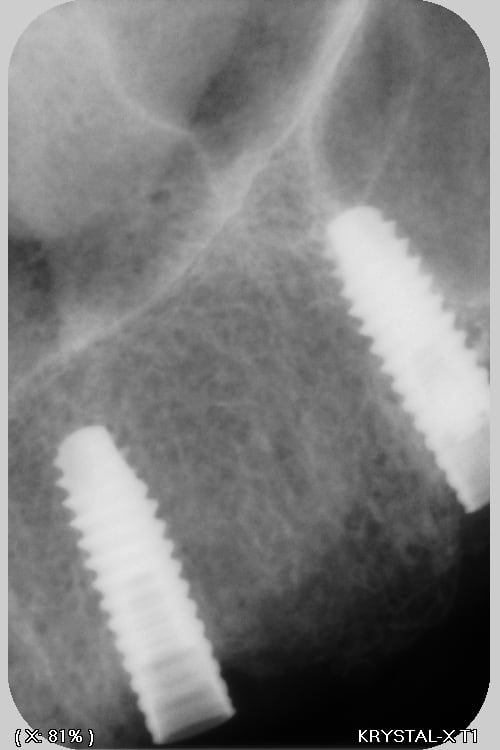

C'est de l'Anthogyr avec des piliers InLink

Il faut utiliser le tournevis Anthogyr pour accès angulé (tête boule)

Effectivement, c'est le seul truc que je n'utilise pas chez eux...c'est très ingénieux, mais dans le cas présenté, ils ont tous cassés..., j'attends de voir la prothèse d'origine pour savoir d'où vient le soucis.